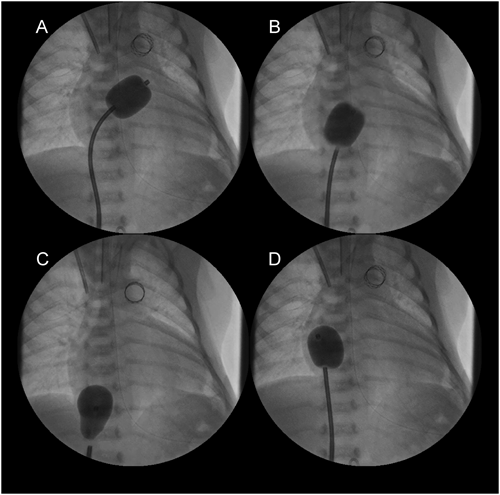

The main pulmonary arteriogram revealed the constriction of the pulmonary arterial side of the arterial duct (AD), which was not covered by the previously implanted stent (A; arrow). The guide wire was formed in vitro into an inverted U-shape to fit the curvature of the AD (B, arrows). During the procedure, blood pressure was maintained at a higher level after intravenous infusion of epinephrine (10 µg), and a stent (6 mm in diameter and 18 mm in length) (Palmaz Genesis® 1860) was delivered into the AD by bare delivery (C) and implanted (D).

2006年10月から2013年10月の間に当院で12症例(Table 5)に施行したDSの最中または後に生じた合併症・問題点をTable 6に示す.最多の問題は手技中の血圧低下であり,12症例中7症例に認められ,その内の5症例はHLHSであった.特に大動脈弁閉鎖では血圧低下から冠血流が低下して重篤な心機能低下をきたし得るので,Bare stent deliveryやエピネフリン静注などの対応を施して手技に臨む必要がある.

HLHSではBil-PAB後であってもカテーテルなどをRVから下行大動脈(DAo)まで進めるとRVのストレッチ,PR・TRの出現などから血圧が低下しやすいので,極力RVをストレッチさせないmaterialsを使用する.人工呼吸管理下の施行が安全だが,鎮静剤等の使用から血管拡張による血圧低下がある場合は昇圧剤を併用して血圧を高めに保つように心掛ける.

Wire: 0.035″ Hanako; Long sheath: 6F Brite tip; Stent: Express™ LD Vascular stent (1880).